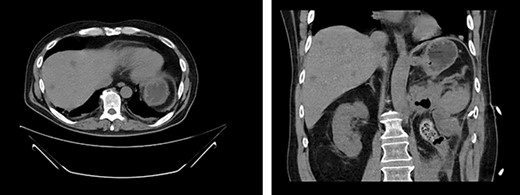

Left renal mass measuring 11 × 9 × 7cm in transverse (left) and coronal (right) planes.

A 52-year-old, previously healthy, Caucasian male presented to the emergency department (ED) with chief complaints of gross hematuria, abdominal pain, vomiting, diarrhea and left flank pain for 3 days. He had neither family history of cancer nor history of exposure to ionizing radiation, arsenic, thorium dioxide or vinyl chloride. He reported exposure to chemical tankers 10 years prior and had recent occupational exposure to paint-thinning agents. Urinalysis on admission showed large blood with later cytology significant for atypical epithelioid cells concerning for neoplasm of the kidney or bladder. Subsequent contrast-enhancedcomputed tomography (CT) of the abdomen revealed an 11-cm left renal mass, 2-cm para-aortic lymphadenopathy and possible invasion of the tail of the pancreas (Fig. 1). He was then referred to urology for evaluation and to discuss treatment options.